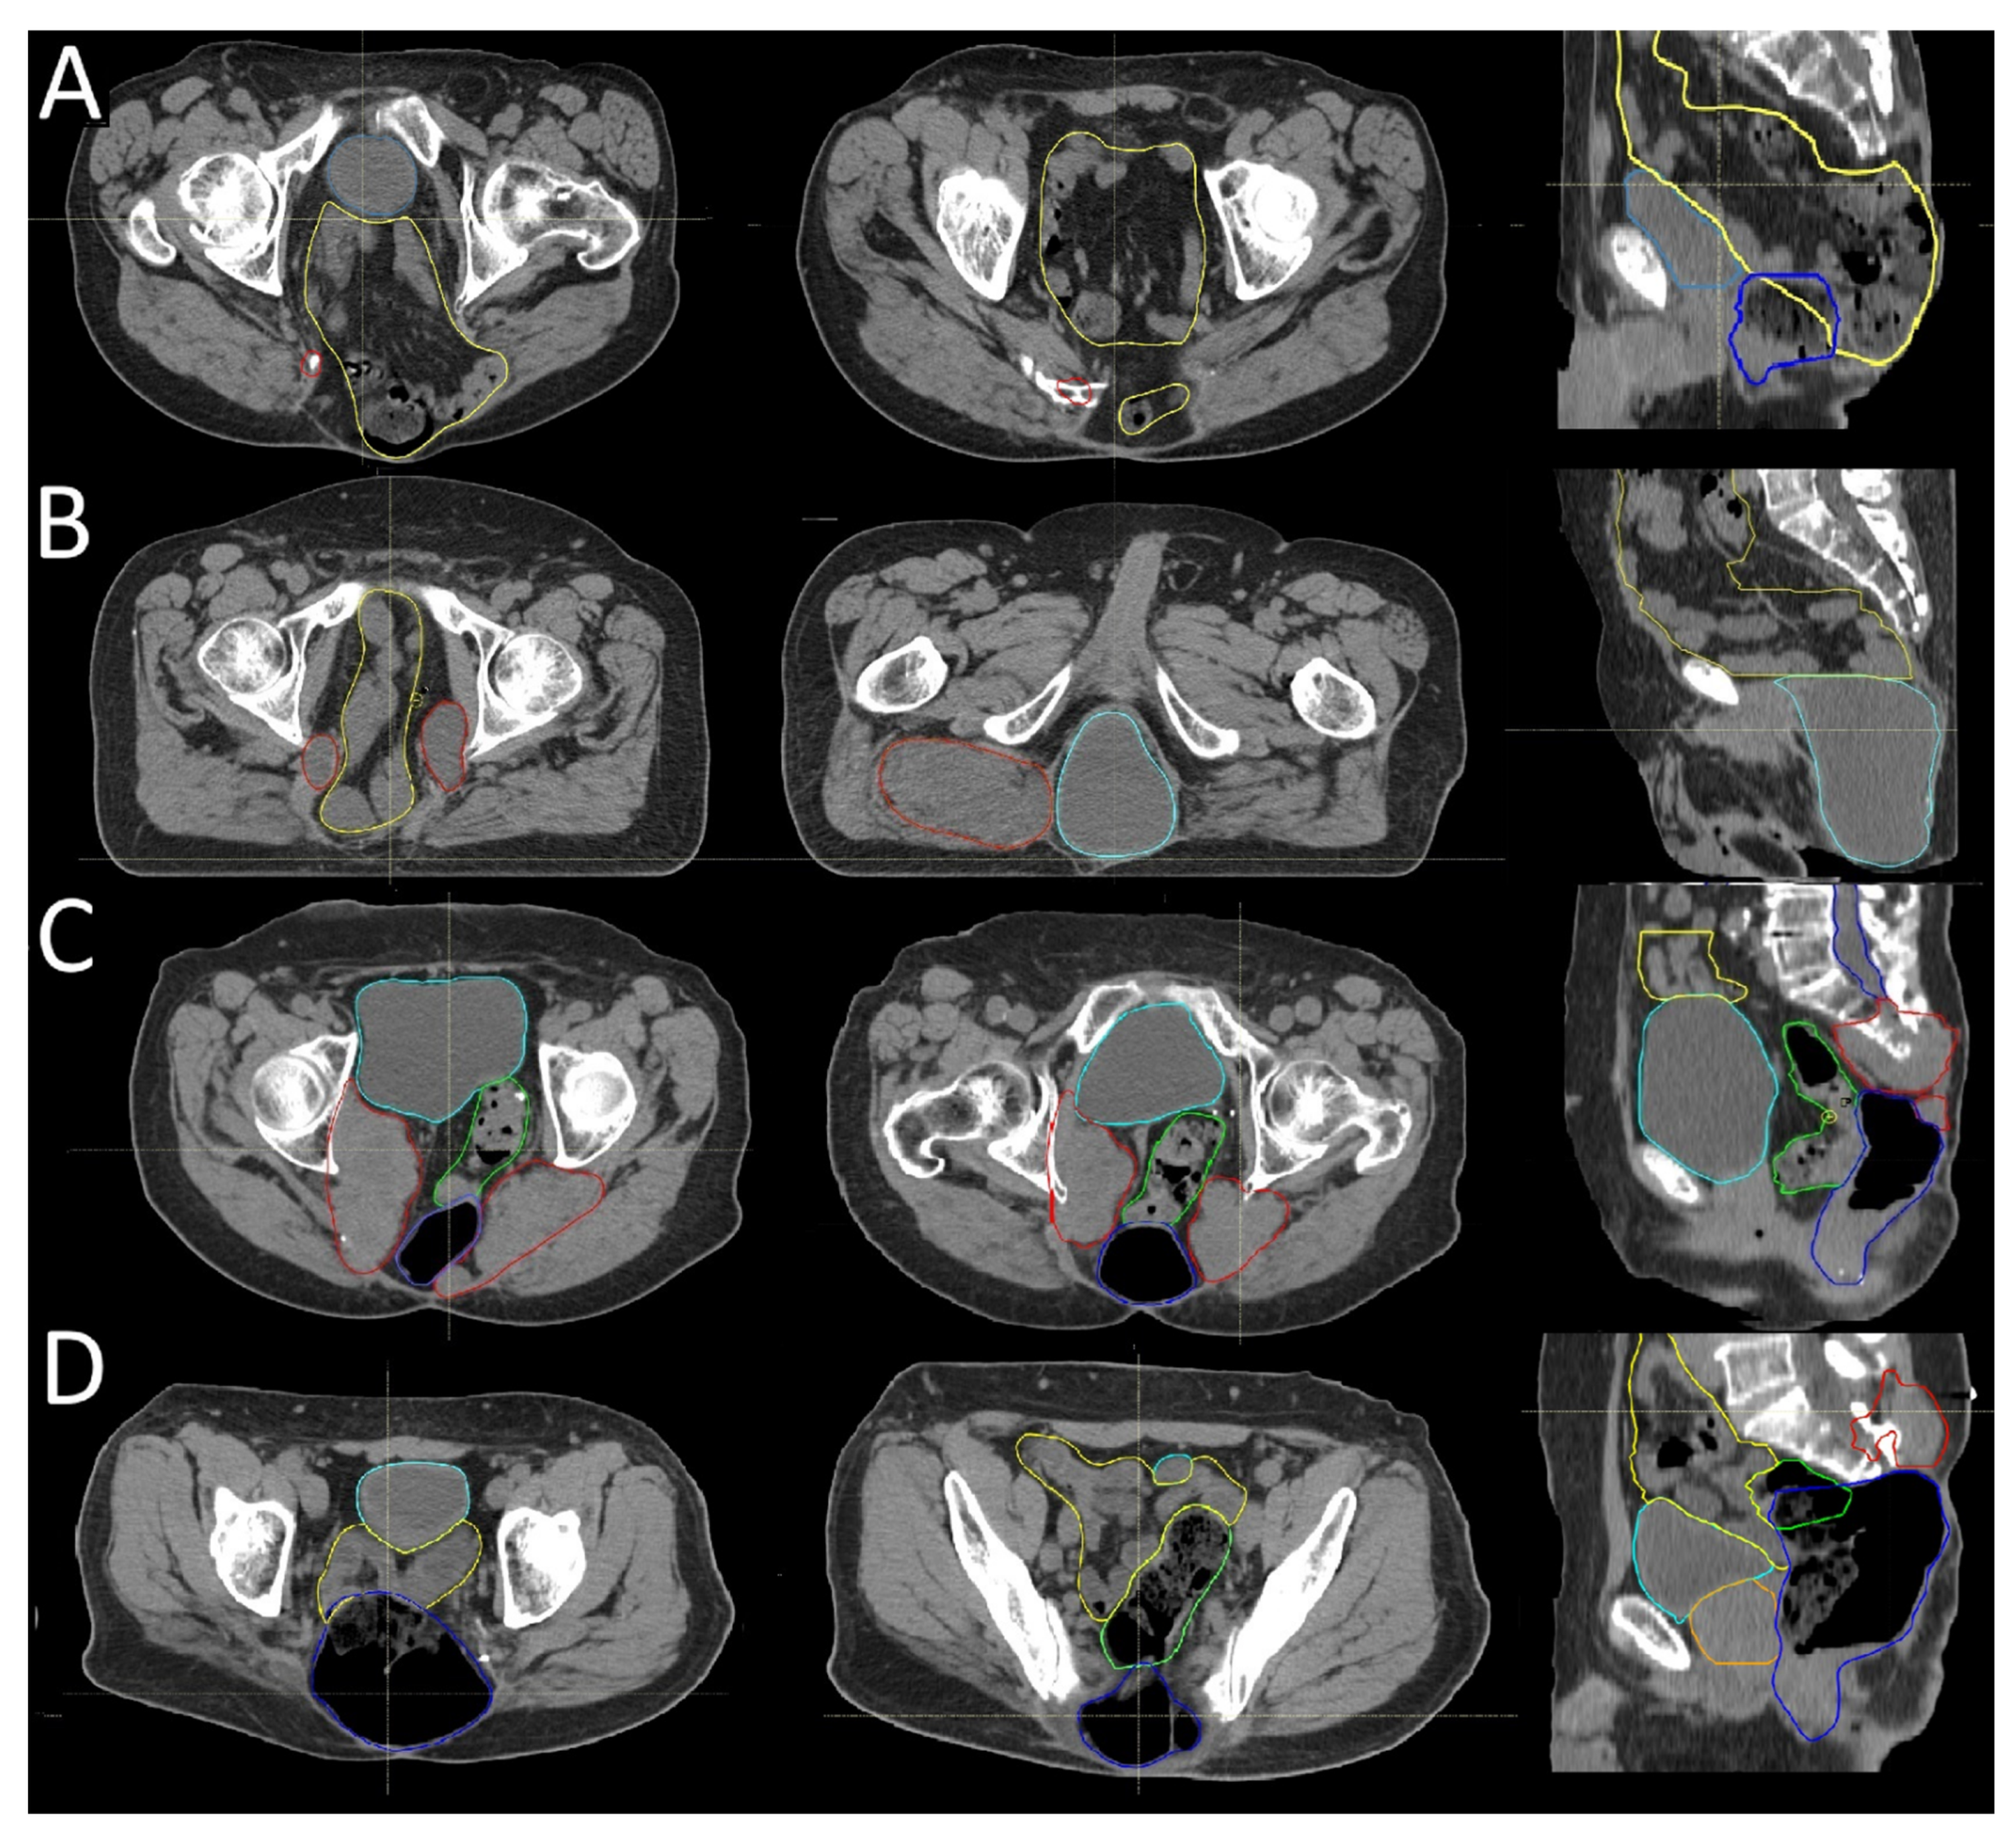

3.2. Recurrence Patterns

3.3. Postoperative Radiotherapy Planning Based on Recurrence Patterns